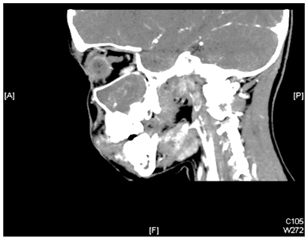

A 9 years old girl, presented with longstanding, left sided nasal obstruction and serosanguinous nasal discharge. She had been experiencing nasal obstruction and intermittent epistaxis for one year already. Her past medical history was otherwise unremarkable. The patient on anterior rhinoscopy, a bulge was detected, arising from the left nasal wall and impinging on the septum. The computed tomography (CT) examination was performed on a spiral scanner. The CT scan obtained following intravenous contrast administration revealed a large, inhomogeneously enhancing mass in the left maxillary sinus and nasal cavity (Figure 1–3). The nasal turbinates and the medial wall of the maxillary sinus had been eroded by the mass. There was also a bony remodeling in the anterior wall of the maxillary sinus. Because of the suspicion of sinonasal cancer, a biopsy was taken to obtain tissue from the nasal cavity and maxillary sinus. However, the biopsy revealed multiple submucosal dilated vessels filled with blood, fibrin deposition and organized thrombi stain for fungal organism negative, findings consistent with hemangioma. The microscopic examination showed dilated sinusoidal vascular channels in the stroma lining with an interconnecting fibrous wall covered with flat endothelium. The Lumina of these spaces were filled with blood. The histologic features were most compatible with cavernous hemangioma (Figure 4). On follow up, patient improvement regarding nasal obstruction and less nasal bleeding.

Figure 3 Sagittal CT revealed a large expansile mass occupying the whole left maxillary sinus